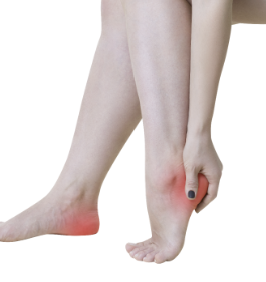

발목 퇴행성 관절염은 발목의 연골과 인대가 부서지거나 마모되어 발생하는 만성적인 관절염입니다. 이 질환은 노화, 스포츠 손상, 다양한 병리적인 원인 등으로 인해 발생합니다. 이 질환은 일반적인 발목염과 달리 연령이 들어갈수록 증상이 악화되어 조작이 어려워지고 일상생활에도 지장을 주는 경우가 많습니다. 발목 퇴행성 관절염의 증상에는 발목통, 경직, 염증, 관절의 강직성, 가동범위 제한 등이 포함됩니다. 이러한 증상은 보통 시간이 지남에 따라 악화됩니다. 적절한 치료 없이 지속되면, 발목 퇴행성 관절염은 관절염증, 연골 손상, 영구적인 관절 손상 등을 유발할 수 있습니다. 적절한 관리와 치료를 통해 증상을 완화시키고, 관절의 기능을 유지하는 것이 중요합니다.

발목 퇴행성 관절염의 증상은 다양합니다. 일반적인 증상은 다음과 같습니다.

- 통증: 발목 부위에 통증이나 불편함을 느끼는 것이 일반적입니다. 통증은 보통 특정한 활동이나 운동 후에 악화됩니다.

- 관절 강직성: 발목이 움직이는 범위가 제한되며, 아침 일어날 때나 긴 시간 앉았다 일어날 때 더욱 뚜렷해집니다.

- 염증: 발목 주변에 염증이 생길 수 있으며, 부음으로 인한 부종과 진통을 유발할 수 있습니다.

- 기능 저하: 발목 관절의 기능이 감소하여 일상적인 활동에 어려움을 느낄 수 있습니다. 예를 들어, 걷거나 계단을 오르내릴 때 어려움을 느낄 수 있습니다.

- 증상 악화: 발목 퇴행성 관절염은 시간이 지남에 따라 악화됩니다. 초기 증상이 가벼울 수 있지만, 지속적인 관리가 없다면 증상이 악화될 수 있습니다.

이러한 증상이 지속될 경우, 진행되는 발목 퇴행성 관절염은 더욱 심화될 수 있으며, 치료 없이는 관절 구조의 영구적인 손상과 관절 운동의 제한이 발생할 수 있습니다. 따라서, 초기 증상이 발생하면 즉시 전문가와 상담하여 적절한 치료와 관리가 필요합니다.